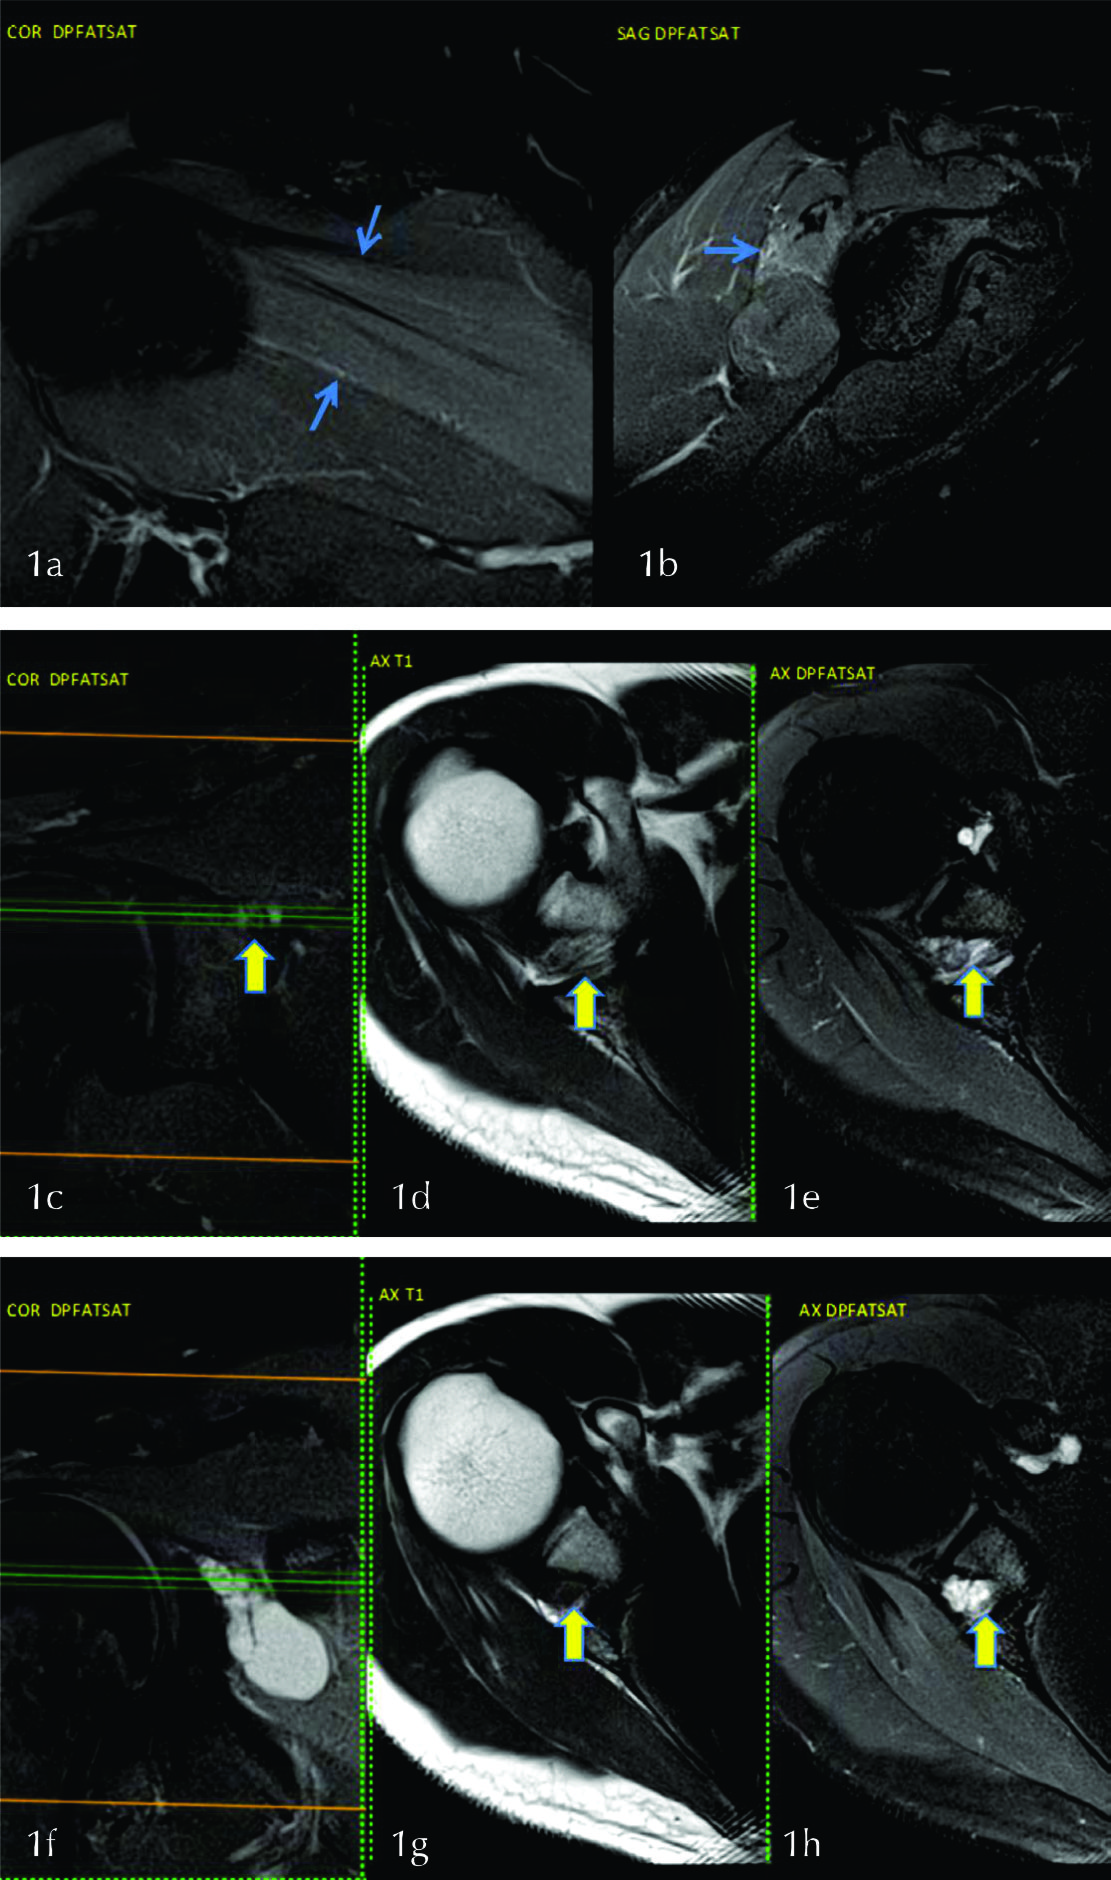

Paciente de 33 años de sexo masculino (SM), que consulta por omalgia derecha post esfuerzo. Se solicita una resonancia magnética (RM) de hombro derecho que muestra edema del musculo infraespinoso (fig. 1 a y b), sin edema en supra, subescapular ni redondo menor lo cual orienta a lesión del nervio supraescapular después de emitir la rama para el supraespinoso: topografía la lesión en la escotadura espino-glenoidea.

En la escotadura espinoglenoidea se identifica el nervio supraespinoso acompañado de la arteria supraespinosa (fig. 1 c,d,e).

Un corte mas abajo, axial y coronal posterior, se ve el nervio supraescapular y delante del mismo un quiste sinovial a nivel de la escotadura espino glenoidea que es la causa de la compresión del mismo (Fig. 1 f,g,h). El músculo infraespinoso presenta edema, sin atrofia en T1 compatible con denervación aguda o subaguda.

Cuando la denervación afecta solamente al infraespinoso se debe buscar la causa de compresión del nervio supraescapular a nivel de la escotadura espino glenoidea donde pueden observarse quistes (sinovial o para labral) que deben diferenciarse de várices u otras lesiones ocupantes de espacio (6).

Figura 1

Se observa leve hiperseñal del musculo infraespinoso (flechas en a y b). Se identifica el nervio supraescapular en la escotadura espino glenoidea (flechas) en los planos coronal (c) y axial (d y e), las líneas en c indican la altura del corte en d y e. Quiste sinovial ocupando la escotadura espino-glenoidea en los planos coronal (f) y axial (flechas en g y h).